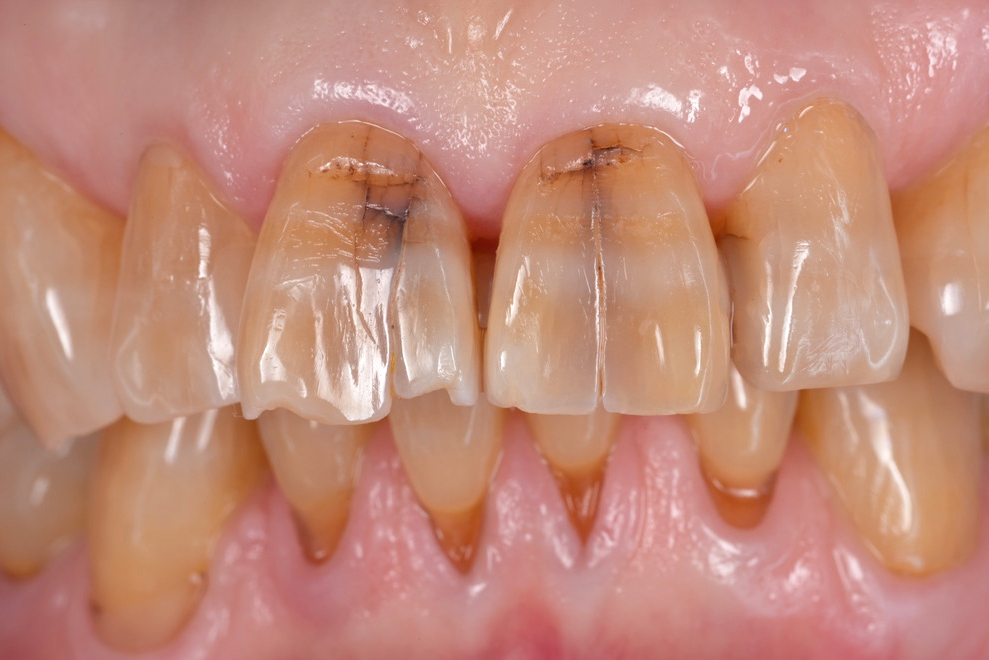

歯のひび割れ・亀裂とは?原因・症状・治療法を歯科医師が解説

歯のひび割れや亀裂は自分ではなかなか気づけないことが多く、発見が遅れてしまうケースもあります。しかし、この状態を放置すると、痛みや知覚過敏を引き起こすだけでなく、最終的には抜歯に至る深刻な事態につながる可能性もあるのです。

歯にできたひびや亀裂(クラック)は、自覚しにくいまま進行することがあり、放置すると虫歯や歯周病の悪化、歯の根が割れるなど深刻なリスクとなります。放っておいても元通りにはならないため、早めの発見と適切な処置が重要です。症状がなくても、定期検診でのチェックが予防につながります。

一度ひびが入ってしまった歯は、皮膚のように自然に元に戻ることはありません。歯には自己修復の力がないためです。小さなひび割れでも、毎日の咀嚼や歯ぎしり、無意識の食いしばりなどの影響で、ひびは徐々に深く広がっていきます。

ひびが進行して歯の中にまで達すると、細菌が侵入しやすくなり、歯の内部で感染が起こるリスクが高まります。最終的には歯の根が割れてしまい、抜歯が必要になるケースもあります。

歯ぎしりや食いしばりによる強い力は、歯に細かいひび(マイクロクラック)を生じさせる大きな要因です。特に、就寝中や集中しているときなど、無意識に強く噛んでしまうことが多く、気づかないうちにダメージが蓄積していきます。

神経を取った歯(失活歯)は栄養が行き渡りにくくなるため、健康な歯よりももろく、ひびや破折のリスクが高まります。また、加齢による歯の質の低下や、過去の治療で入れた詰め物・被せ物の境目からひびが広がるケースも見られます。

歯のひび割れの深さによって、現れる症状はさまざまです。初期の軽いしみる感覚から、強い痛みや歯ぐきの腫れといった深刻なサインまで、進行度に応じて変化します。放置すると抜歯が必要になるケースもあるため、早めの対応が欠かせません。

歯の表面にできる浅いひび割れは、エナメル質やその内側の象牙質に生じます。この段階では、冷たいものが一時的にしみる程度の軽い知覚過敏や咬合痛が現れることがあります。